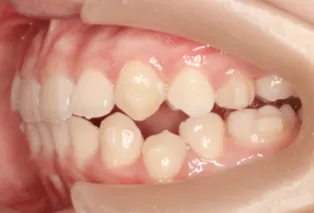

Photos intra-orales